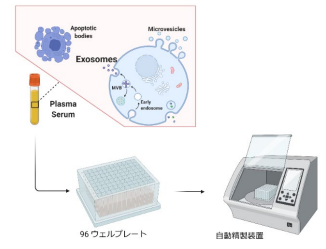

細胞外小胞の新しい捕捉方法を開発~ナノワイヤによって捕捉する細胞外小胞を、がん診断の新しい指標へ~

細胞外小胞(EV)の新しい捕捉方法を開発し、当該方法で捕捉するEVのmiRNA(マイクロRNA)や膜たんぱく質の発現量が...

エクソソーム(細胞外小胞)の多検体自動精製技術開発に成功

一度に96検体からエクソソームを精製することができる自動精製技術の開発に成功した。